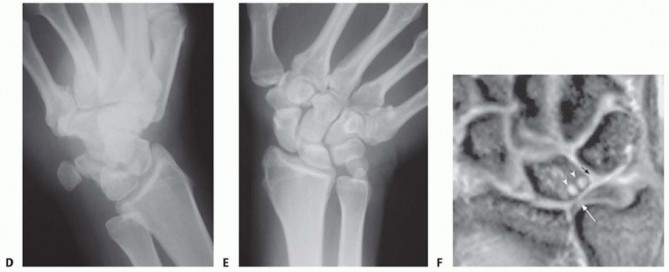

Imaging serves as our architectural blueprint for surgical planning. We mandate a comprehensive plain radiographic series. This begins with strictly neutral rotation posteroanterior (PA) and lateral views of both wrists to accurately assess static ulnar variance and the morphology of the sigmoid notch. However, static views are insufficient. We must obtain a pronated grip view (the clenched fist PA). As Tomaino and others have definitively demonstrated, active power grip forces the radius proximally relative to the ulna, increasing dynamic ulnar variance by an average of 2.5 mm. This view often unmasks profound dynamic impaction in wrists that appear neutrally variant on resting films.

Advanced imaging and diagnostic modalities are frequently employed to refine our surgical strategy. High-resolution Magnetic Resonance Imaging (MRI), particularly when enhanced with intra-articular contrast (MR arthrography), is invaluable. It allows us to detect central TFCC perforations, evaluate the integrity of the intrinsic carpal ligaments (scapholunate and lunotriquetral), and identify early subchondral cystic changes or bone marrow edema in the proximal ulnar aspect of the lunate—the hallmark of advanced impaction. When diagnostic uncertainty persists, or when concomitant intra-articular pathology requires debridement, we utilize wrist arthroscopy. Arthroscopy remains the gold standard for directly visualizing chondral damage, assessing the trampoline effect of the TFCC, and confirming the precise Palmer classification prior to executing the extra-articular osteotomy.